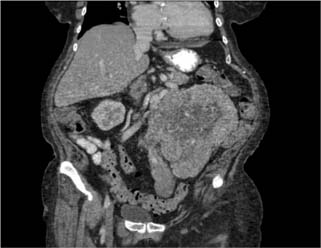

The patient’s medical and surgical history was unremarkable except for insulin independent diabetes mellitus. A left-sided abdominal mass was palpable on physical exam. Further evaluation revealed no evidence of distant metastatic disease on CT imaging of the head, chest x-ray, recent CT chest, or CT abdomen and pelvis. Magnetic resonance imaging of the abdomen, obtained approximately 1 month prior to her surgery, did not reveal any evidence of left renal vein involvement. After extensive counseling and a thorough discussion of the risks involved and the benefits, she opted for surgical extirpation of her locally advanced renal mass and regional lymphadenopathy. She underwent an open left radical nephrectomy, total abdominal hysterectomy with bilateral salpingo-oophorectomy, and retroperitoneal and pelvic lymph node dissection. Intraoperatively, the mass was found to be large and bulky, extending toward the pelvis and invading the local structures. The ascending colon was reflected medially, at which time the mass was noted to be involving part of the mesentery, which required resection. Once the hilum was controlled, the mass was dissected down toward the pelvis and was noted to be involving the uterus and the bilateral ovaries. A supracervical hysterectomy with bilateral salpingo-oophorectomy was performed. The left gonadal vein with tumor thrombus was mobilized and the mass was dissected off the lateral abdominal wall, which allowed the whole specimen to be elevated en bloc until it was completely free. A retroperitoneal and left pelvic lymph node dissection was completed, and all specimens were sent for pathologic examination. Estimated blood loss was 750 mL, and there were no intraoperative or postoperative complications. The patient had an uneventful 5-day hospital course and was discharged to a subacute rehabilitation facility. Upon further review of the abdominal and pelvic CT scan, there was a heterogeneous appearance of the uterus, which had been assumed to be related to fibroids (Figure 2).

Figure 2: Axial view of computed tomography of the abdomen and the pelvis revealing a heterogeneous appearance of the uterus.